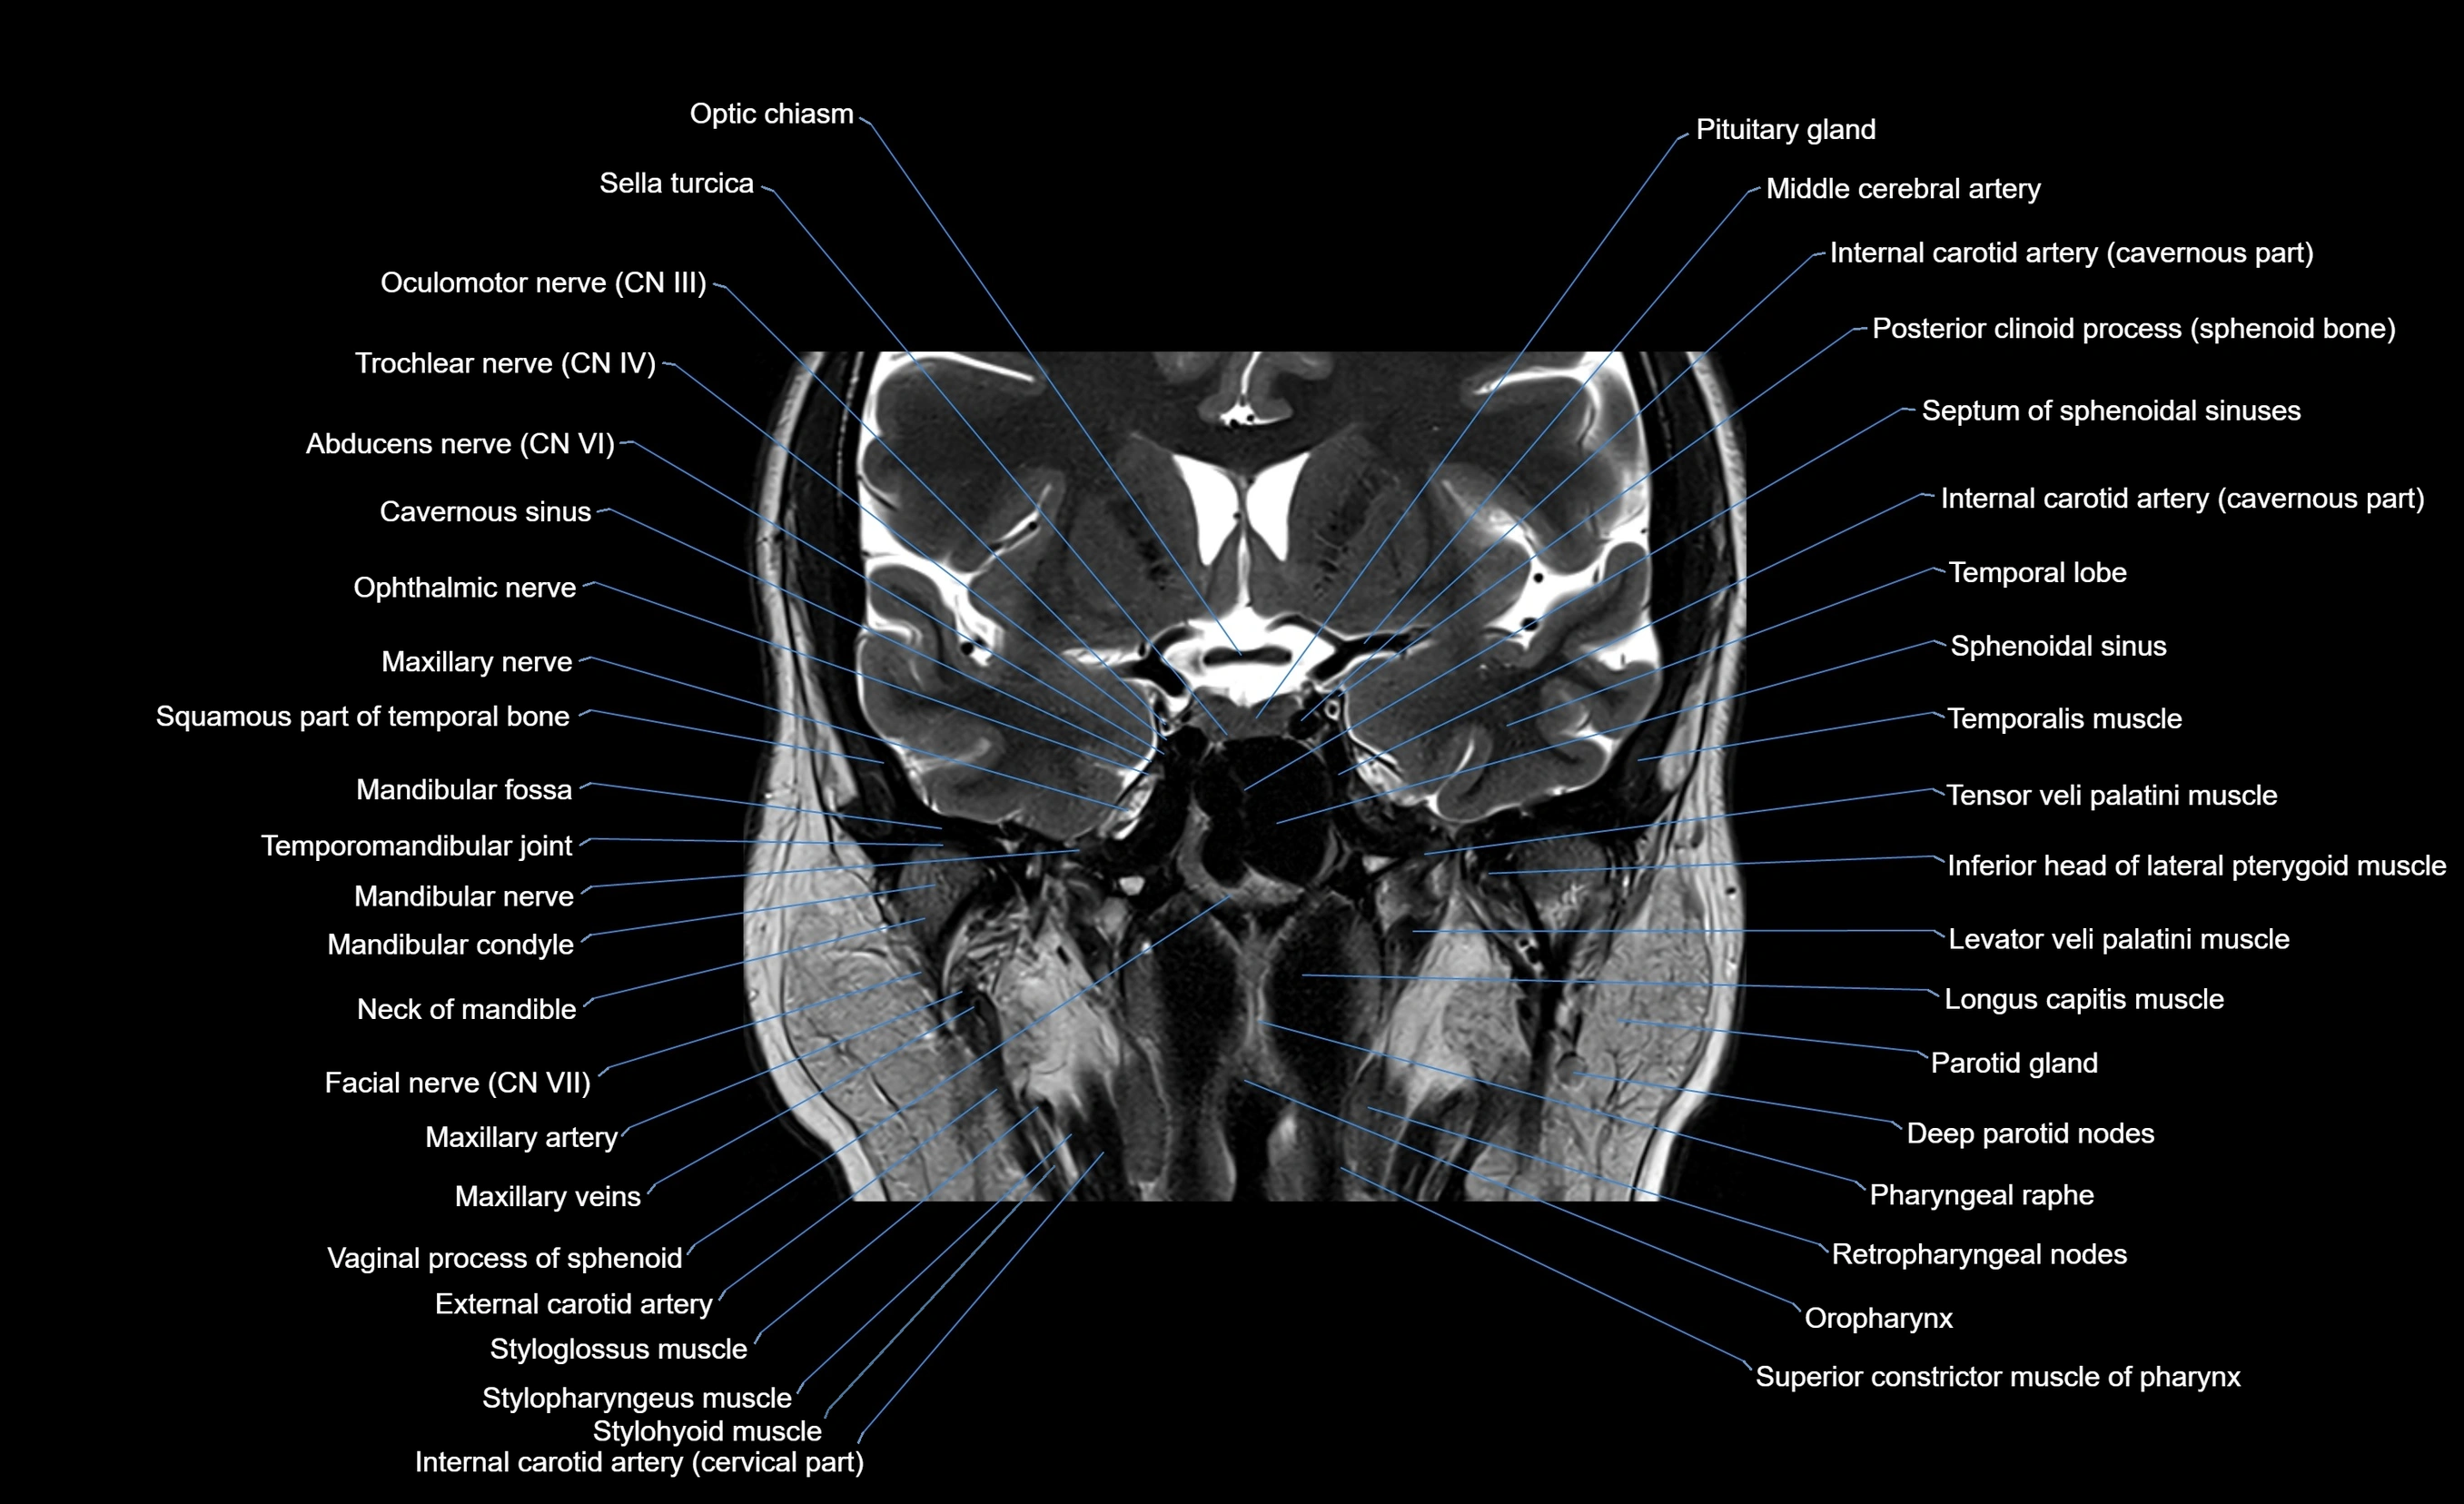

- Abducens nerve (Cranial nerve VI)

- Internal carotid artery (cavernous part)

- Internal carotid artery (cervical part)

- Mandibular nerve

- Mandibular condyle

- Mandibular fossa

- Maxillary nerve

- Maxillary artery

- Maxillary veins

- Levator veli palatini muscle

- Inferior head of lateral pterygoid muscle

- Longus capitis muscle

- Parotid gland

- Oropharynx

- Superior constrictor muscle of pharynx

- Styloglossus muscle

- Stylohyoid muscle

- Stylopharyngeus muscle

- Trochlear nerve (Cranial nerve IV)

- Oculomotor Nerve (Cranial Nerve III)

- Optic chiasm

- Sella turcica